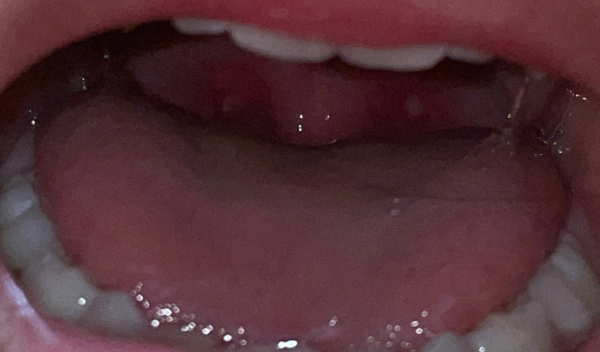

대표적인 수족구 증상으로 손, 발, 입 안에 수포성 발진이 나타납니다. 수족구병은 4세 이하의 소아에게 꾸준히 발발하고, 수족구에 감염된 아이를 돌보다 면역력이 약한 성인 역시 감염될 수 있습니다.

미열이 있는 4세 미만 어린이의 손, 발, 입 주변에 발진이 수포성으로 있는지 잘 살펴보고 수족구병임을 진단합니다.